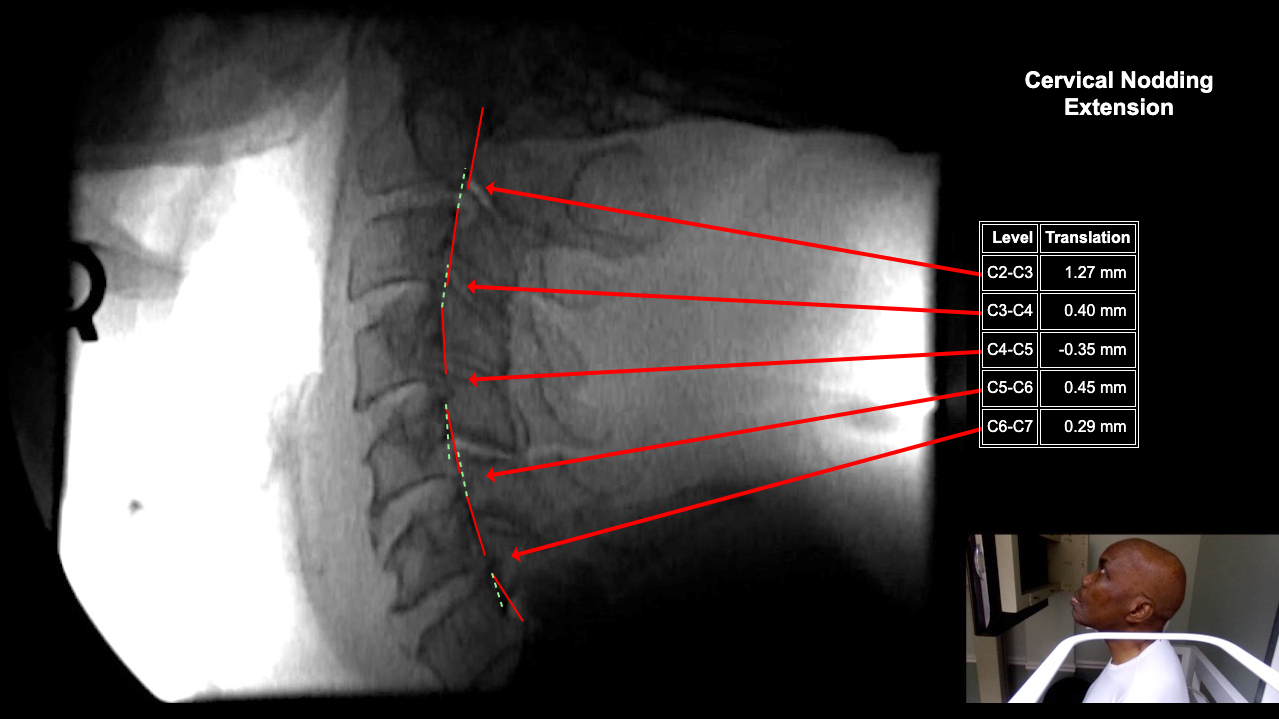

Image Name Image Type Image